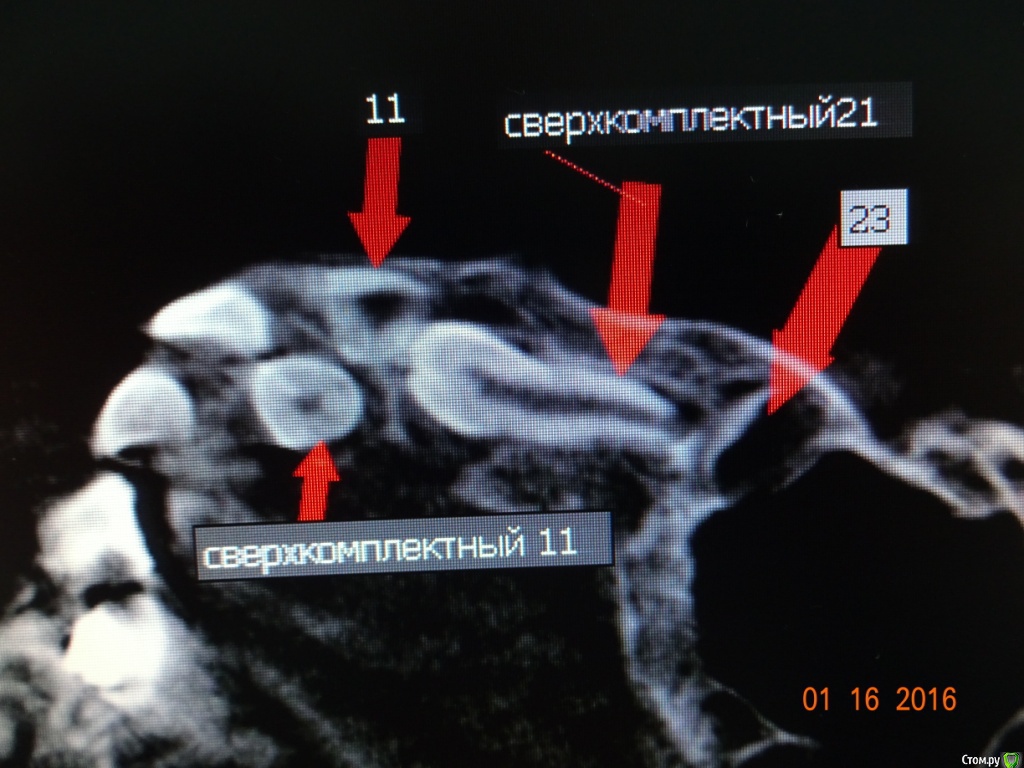

Dok22 Опубликовано 11 января, 2017 Поделиться Опубликовано 11 января, 2017 Это не премоляр просто так виден 2-х мерный срез нужно КТ его грамотная интерпретация и хороший хирург.Сверхкомплектный удалять надо он блокирует 21 и 22. Ссылка на комментарий

Dok22 Опубликовано 12 января, 2017 Поделиться Опубликовано 12 января, 2017 С одной стороны вы правы риск повредить 21 22 есть,но если сверхкомплектный 21 сформируется полностью все будет сложнее сейчас при наличии грамотного КТ и хирурга зачаток сверхкомплектного 21 убрать проще.Убирал подобное в 6 и 9 лет в 9 сложнее. Попробую найти КТ выложить. Ссылка на комментарий

Dok22 Опубликовано 21 января, 2017 Поделиться Опубликовано 21 января, 2017 Это фотоаппарат врет, вмешательство от 4.01.2017. Родители получили инструкции+скайп ждем.Док не надо бояться начните с простого,кто если не мы? Делал так :1) Перед вмешательством седация.Анестезия.2) Вырезал лоскут с надкостницей, создав окно примерно 1кв.см.(чтоб не бороться с краями раны, я так и 8 убираю)3) Компактостеотомия ультразвуковым алмазом(кость мягкая режется легко ,им же режем сверхкомплектный зуб бывает вертится в ране можно фиксировать гладилкой)4) Сегментируем зуб,выбираем фрагменты(обязательно тщательно убрать ростковую капсулу сверкомлектного,обильно промыть водой.Аккуратно проконтролировать отсутствие ростковой зоны!!!)5) Рана не ушивается, только тампонада как при обычном удалении.6) Инструкции родителям(отеки,субфебрильная температура,болезненность это нормально не более суток,при болях детское) Вам нужен ассистент,тонкий кровоотсос,обычный слюноотсос,тонкий элеватор(3-4милиметра) и самое важное ТЕРПЕНИЕ.Спрашивайте. 1 Ссылка на комментарий